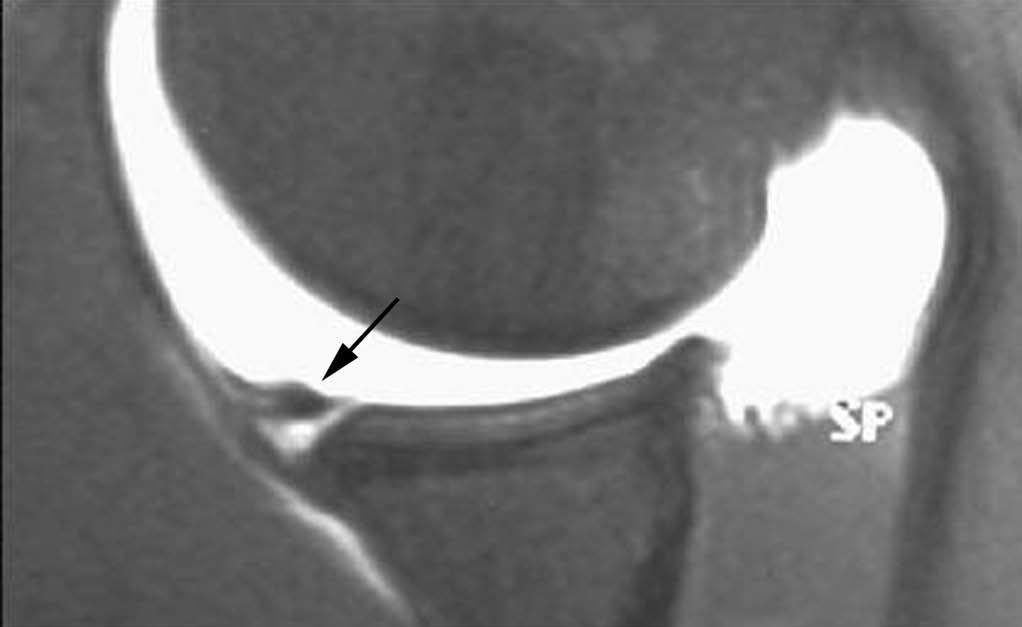

Esta lesión se produce a consecuencia de una tracción repetitiva de la unión cápsulo-perióstica posterior, produciéndose una osificación semejante a un espolón óseo (fig. 15).

Fig. 15.--Lesión de Bennett. Tomografía axial computarizada (TAC) axial (A) y resonancia magnética (RM) T1 axial (B) que revelan la presencia de un «espolón» óseo adyacente al borde glenoideo posterior (flechas en A y B). Nótese la ausencia de una lesión del labio glenoideo posterior en B.